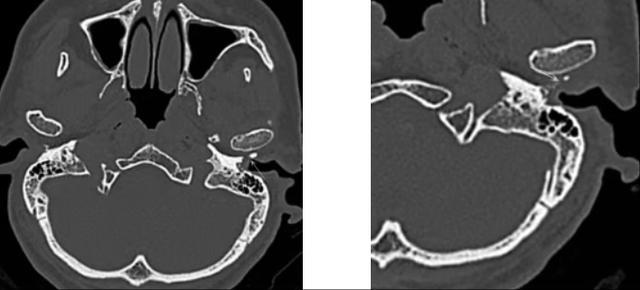

67岁燕大伯因“左耳疼痛不适反复1月加重3天”来桃源县中医医院耳鼻咽喉头颈外科门诊就诊,经初步检查,医生考虑燕大伯耳朵情况为“外耳道胆脂瘤”,于是建议住院进一步检查治疗。入院后完善术前相关检查,CT发现燕大伯左耳道骨质明显破坏,且范围较大,前壁及下壁可见骨质裸露,缺损,部分坏死。庆幸的是鼓膜及鼓室,听骨无明显破坏。

(▲术前CT检查)